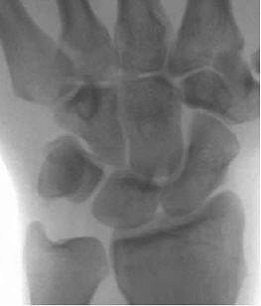

| The advantages of direct MR arthrography included clear visualization of synovial reaction and chondromalacia, and marrow edema, said Shuang and Xiaoyuan in their RSNA presentation. Images courtesy of Dr. Chen Shuang. |

On MR arthrography, the readers saw high signal intensity of contrast media at the ulnar insertion or radius attachment of the TFCC. Synovial reaction, chondormalacia and marrow edema were also clearly depicted on T2-weighted imaging and direct MR arthrography.

Shuang and co-author Dr. Fen Xiaoyuan suggested that when assessing for peripheral TFCC tears, imagers would find more diagnostic value from the high signal intensity at the radius attachment than at the ulnar insertion. They concluded that direct MR arthrography can reveal the peripheral attachment of the TFCC. Shuang told AuntMinnie.com that direct MR arthrography is now the preferred modality for TFCC imaging at his institution.